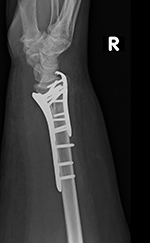

plate and a separate screw), and an oblique angled 3.5 T-plate for fixation of distal radius fractures (figure: wrist T-plate; figure: variable angle volar distal radius locking plate).

53 year-old woman with distal right radial and ulnar fractures. There is an ulnarly applied hook locking compression plate and screws and a variable angle volar distal radius locking plate and screws. |